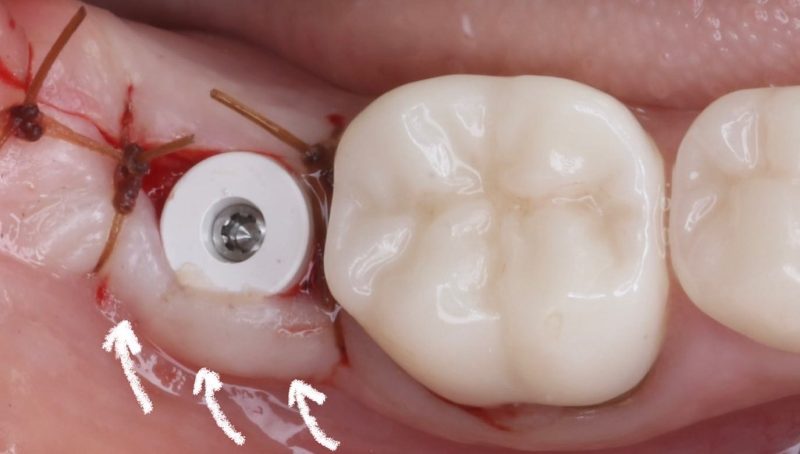

When dealing with these cases, I intentionally make my incision more lingual to preserve as much tissue as possible for the buccal side. I place the implant 1.5mm subcrestal to ensure proper stability and room for bone and soft tissue regeneration. Once the implant is in place, I use a healing cap and reposition the tissue, which allows us to achieve a thick, healthy band of keratinized tissue on the buccal.